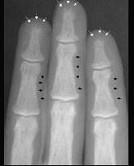

问题 女性,50岁,反复发作尿路结石,骨痛,骨骼X线示骨膜下皮质吸收。实验室检查:高钙血症,血清碱性磷酸酶↑,皮质醇抑制试验血清钙不下降。诊断考虑()

选项 A.原发性甲状旁腺功能亢进症 B.继发性甲状旁腺功能亢进症 C.三发性甲状旁腺功能亢进症 D.骨软化症 E.维生素D缺乏症

答案 A